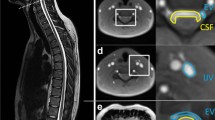

We routinely obtain contrast-enhanced T1-weighted images, with three-axis motion-sensitized driven equilibrium (MSDE) applied, 4 h after intravenous gadolinium-based contrast agent (GBCA) injection via 3-T magnetic resonance imaging (MRI) when endolymphatic hydrops is suspected in patients with symptoms such as dizziness or tinnitus. MSDE suppresses the signal of blood flow through the vessel lumen. We noticed a high-signal region surrounding the signal-suppressed diploic veins on images with MSDE. The space surrounding the diploic veins (Fig. 1) may play a role in waste excretion and immune responses, similar to the perivascular spaces of the brain, as in the parasagittal dura (PSD) and skull–meninges connections. However, to date, no report has quantitatively evaluated the volume of this space. Therefore, this retrospective study aimed to examine the distribution and volume of the space surrounding the diploic veins where the GBCA was distributed and to analyze its spatial characteristics.

Highlighted space surrounding the lectin-labeled diploic vein in the tissue specimen of the human skull labeled with LYZ2 and lectin (reprinted and modified from a previous report [1] under Creative Common Attribution 4.0 International License)

Transverse MSDE T1-weighted images with anonymized patient information were imported into 3D Slicer software (version 5.2.2; available at https://slicer.org). The high-signal areas surrounding the diploic veins were enclosed as regions of interest (ROIs) using a threshold-based algorithm for the slices above the superior border of the lateral ventricles (Fig. 2). The algorithm extracted regions with signal values higher than a predetermined value and then removed irrelevant structures; it was constructed with reference to previous reports [7, 8]. To avoid contrast areas other than the space surrounding the diploic veins and improve reproducibility, measurements were obtained only for high-signal areas with diameters of ≥2 mm. Additionally, reticular high-signal regions exceeding the threshold (Fig. 3) observed within the cranial diploe of certain participants, whose association with the diploic veins was uncertain, were excluded from measurement to prevent potential overestimation. The volume of the ROIs was calculated and recorded using the functions in 3D Slicer.

This study has some limitations. First, selection bias may have existed because all the included participants were patients with suspected endolymphatic hydrops, and none were completely healthy. Second, there is no standardized way to spend 4 h after GBCA injection. The effects of movement, eating, and drinking may be confounding variables that require further investigation. Third, the lack of histologic evidence regarding the space surrounding the diploic veins prohibits definitive determination of its nature, raising the possibility of alternative structures, such as bone marrow. However, given that the high-signal regions exceeding the threshold on the MSDE T1-weighted images were predominantly observed surrounding the diploic vein (Fig. 2), and reticular high-signal regions exceeding the threshold (Fig. 3) were only sporadically detected in certain participants, we consider it unlikely that they represent bone marrow. Fourth, volume measurements were obtained only for the slices above the superior margin of the lateral ventricles, and not all of the cranium could be evaluated. Fifth, the space surrounding the diploic veins, which were <2 mm in diameter or indistinguishable from the reticular high-signal regions exceeding the threshold, was not measured and may be underestimated.